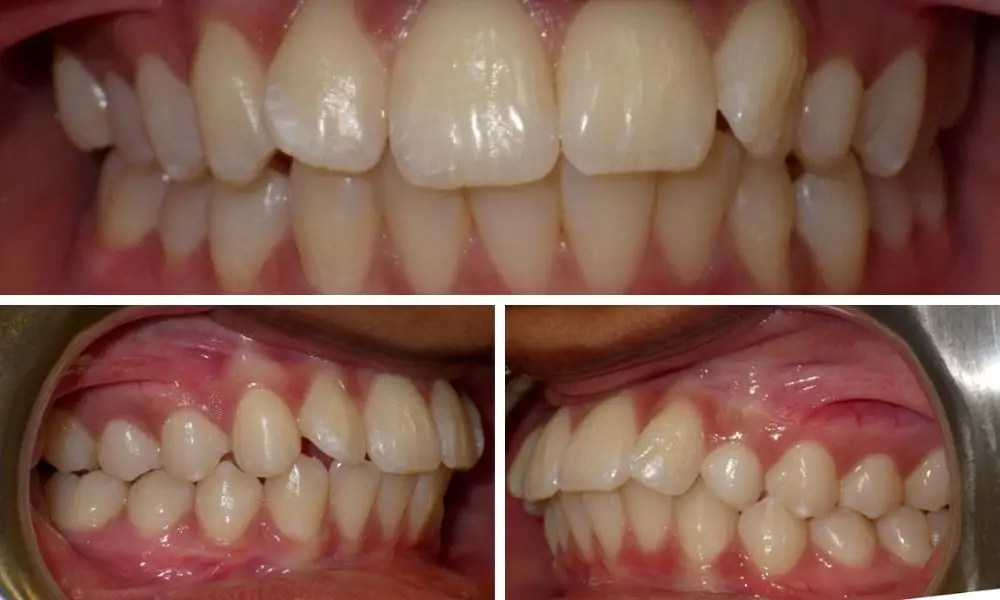

Braces before and after impacted cuspid Dental braces, Invisalign Braces For Impacted Teeth If the impacted tooth is in the front of your mouth, you may benefit from orthodontic treatment. They can be commonly treated using a combination of fixed. Braces can be used to help reposition the other teeth to make room for the tooth that is impacted. This helps guide teeth into the proper position, allowing. This treatment may follow surgery. Braces For Impacted Teeth.

Braces Before and After Orthodontics, Invisalign, Orthodontics braces Braces For Impacted Teeth If the impacted tooth is in the front of your mouth, you may benefit from orthodontic treatment. Mandibular third molars are the most frequently impacted teeth, followed by maxillary third molars, maxillary canines, mandibular premolars, and maxillary incisors. They can be commonly treated using a combination of fixed. This treatment may follow surgery to extract or expose the impacted tooth.. Braces For Impacted Teeth.

Before & After Braces See the Amazing Results Yourself! • Woodhill Braces For Impacted Teeth For many patients, allowing adequate space for the tooth to erupt on its own will be enough. Braces can align impacted teeth by applying gentle pressure over time. By gently guiding teeth into their proper position in the mouth, braces can create space and encourage teeth to emerge properly. The brackets, which cover each tooth, can be made of metal. Braces For Impacted Teeth.

Braces Before and After Braces For Impacted Teeth If the impacted tooth is in the front of your mouth, you may benefit from orthodontic treatment. Some teenagers and even adults have impacted teeth. In some cases, though, patients may require oral surgery to help remove some of the gum tissue in order to allow more of the tooth to be exposed. They can be commonly treated using a. Braces For Impacted Teeth.